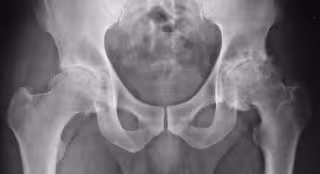

Las inyecciones de esteroides en la cadera y la rodilla para tratar la artrosis pueden dañar las articulaciones

Artrosis - FLICKR/SILVANA CIARDULLO - Archivo

La artrosis de cadera y rodilla son trastornos comunes y debilitantes de las articulaciones. Los médicos a menudo inyectan corticosteroides antiinflamatorios en la articulación para tratar el dolor y la inflamación asociados con esta patología.